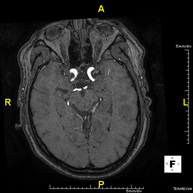

- RM Cerebral (craneal)

Prueba diagnóstica no invasiva que consiste en la obtención de imágenes de alta definición anatómica del cerebro mediante el empleo de un campo electromagnético y ondas de radio (con un emisor y un receptor). No utiliza radiación ionizante. Indicaciones: problemas vasculares, pérdida de memoria, epilepsia, cefalea, malformaciones, sospecha de tumor, meningitis.

- Angio-RM intracraneal

Prueba diagnóstica no invasiva que consiste en la obtención de imágenes de alta definición anatómica de las arterias cerebrales mediante el empleo de un campo electromagnético y ondas de radio (con un emisor y un receptor). No utiliza radiación ionizante. En la mayoría de los casos es necesario el empleo de contraste paramagnético (Gadolinio). Permite un estudio angiográfico no invasivo gracias a la inyección de Gadolinio con posterior reconstrucción en 2D y 3D, gracias a estaciones de trabajo especializadas. Indicaciones: malformaciones vasculares, aneurismas de arterias cerebrales, arteriosclerosis.